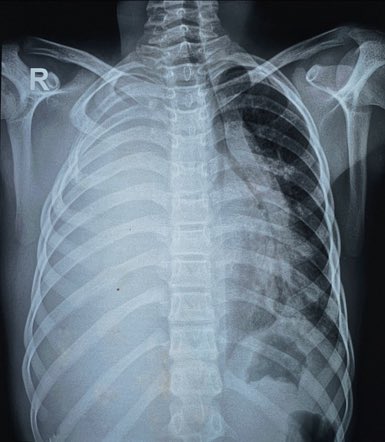

RADIOLOGISTS@DrAyubaD·

EMERGENCY 🆘 A 25y old man was brought in with Acute abdomen. Abdominal X-rays erect and supine as well as chest X-rays were requested. Chest X-ray shown below. What is the most Important finding shown here ? What’s the diagnosis ?